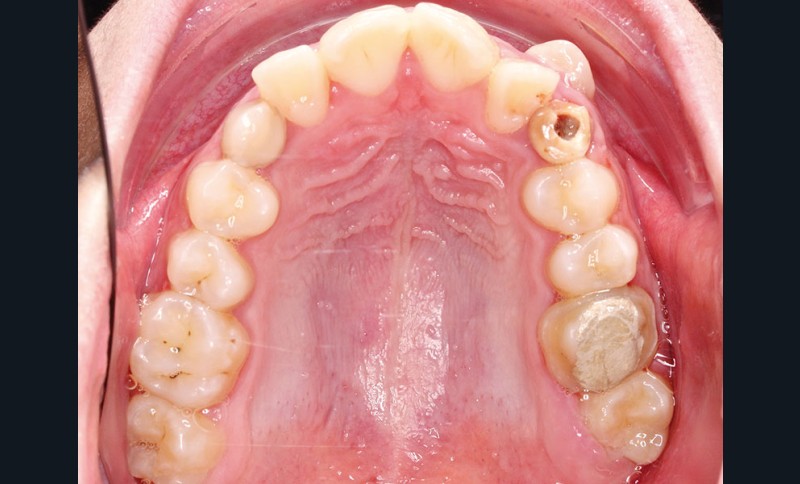

• Endo-buccal : Younesse présente un contrôle de plaque dentaire insuffisant, la persistance de 53 et 63, des soins en cours de réalisation sur 26 et 36, un encombrement maxillo-mandibulaire avec infravestibulotopie de 23 et une suspicion d’inclusion de 13 sur un schéma de Classe II subdivision droite (fig. 3 à 7).